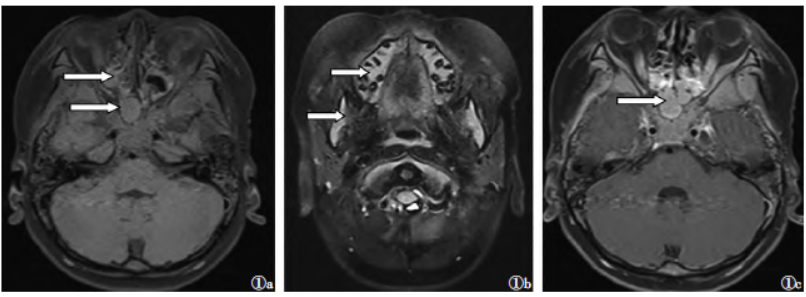

图1编号2患者,男,4岁7个月,急性髓细胞性白血病(AML)图1a脂肪抑制T1WI序列示副鼻窦腔(箭头)、左颞部脑外间隙(箭头)团块状均匀等及等高信号图1b脂肪抑制T2WI序列示下颌骨信号增高图1c增强扫描病灶呈均匀显著强化

6例GS患儿的影像学表现与免疫组化检查结果见表1。6例病灶在体部及四肢均表现为软组织密度影,CT值30~55HU,1例病灶中心出现坏死区,余病灶性质较均匀,但范围较大,直径2.6~18.3cm,呈结节状或团块状改变,境界清晰或模糊,邻近骨质可伴溶骨性改变。MRI对比同层肌肉或皮质均呈等、等高信号;增强扫描呈不均匀明显强化。6例瘤细胞呈圆形、卵圆或形态不规则,包浆少,核分裂可见,弥漫性分布。骨髓活检均见幼稚细胞弥漫增生。